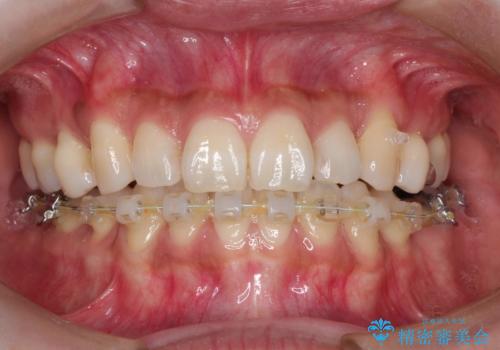

ハーフリンガル抜歯矯正 八重歯を改善する

- ハーフリンガル

- 小臼歯4本抜歯によるハーフリンガル・ワイヤー矯正を計画した。

シビアな八重歯がきれいに歯列にはいることにより、笑った時の印象などもかなり大きく変わります。